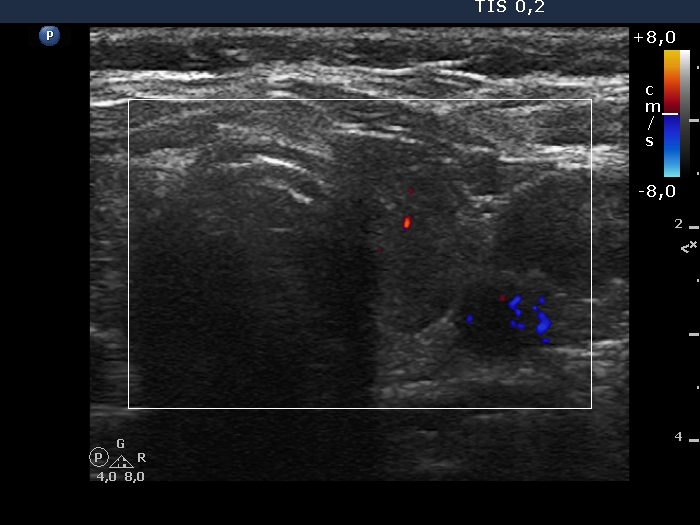

Lymphocytic thyroiditis - case 1442

Follow-up examination 7 years after the first one (ultrasonographic picture 6)

Left lobe, transverse scan, color Doppler mode. The vascularity is scanty.